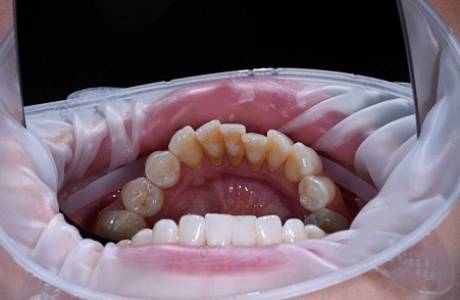

После лечения

Пациенту проведена комплексная гигиена полости рта на аппарате Air Flow, сняты налет и зубные отложения (зубной камень), проведена реминерализующая обработка.